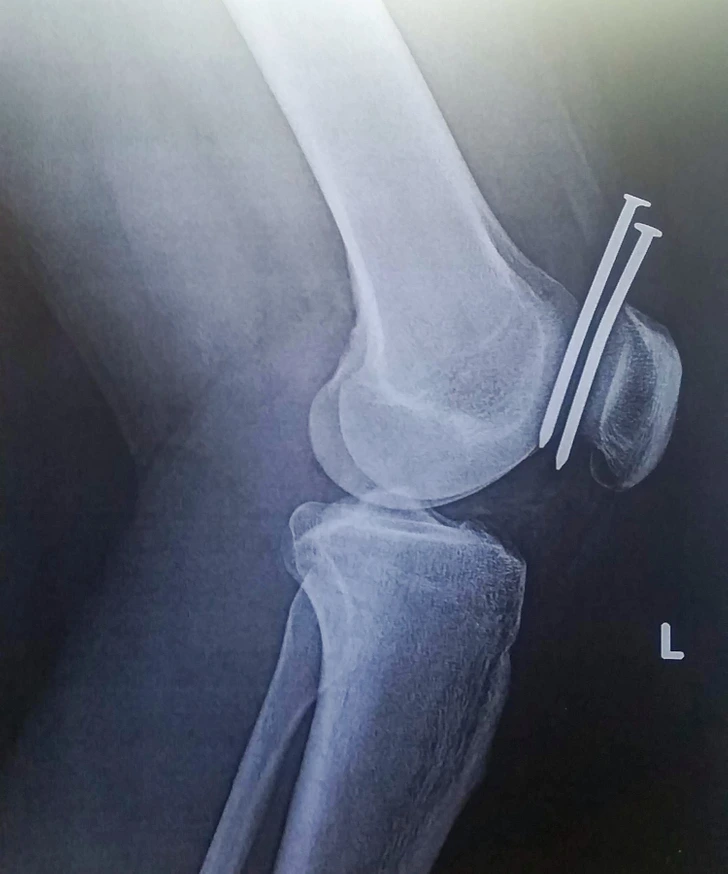

#7 Ešte šťastie, že netrafili kosť